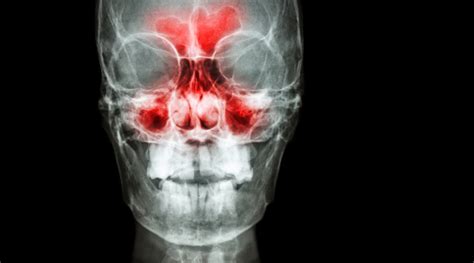

La sinusitis maxilar se define como la inflamación de la mucosa que recubre los senos maxilares. Estos senos son cavidades aéreas que se comunican con las fosas nasales y forman parte de los senos paranasales. Asegurar el cuidado y bienestar de estos senos es fundamental ya que tienen importantes funciones a la hora de respirar, masticar, hablar u oler.

Una sinusitis es una inflamación de la mucosa que recubre los senos paranasales (senos maxilares, etmoidales, frontales y esfenoidal).